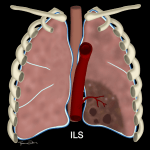

Phổi Biệt Lập | Bài giảng CĐHA *

Phổi biệt lập (Pulmonary Sequestration) là bệnh lý bẩm sinh ở phổi. Phổi biệt lập là khối nhu mô phổi bất thường không có chức năng hô hấp, không thông với cây phế quản, được nuôi bởi một hoặc nhiều nhánh động mạch hệ thống. Phổi biệt lập có thể ở dưới dạng một khối nhu mô phổi loạn sản, thường là dạng nang, nhưng cũng có thể biến chứng nhiễm trùng, thoái hóa ác tính…